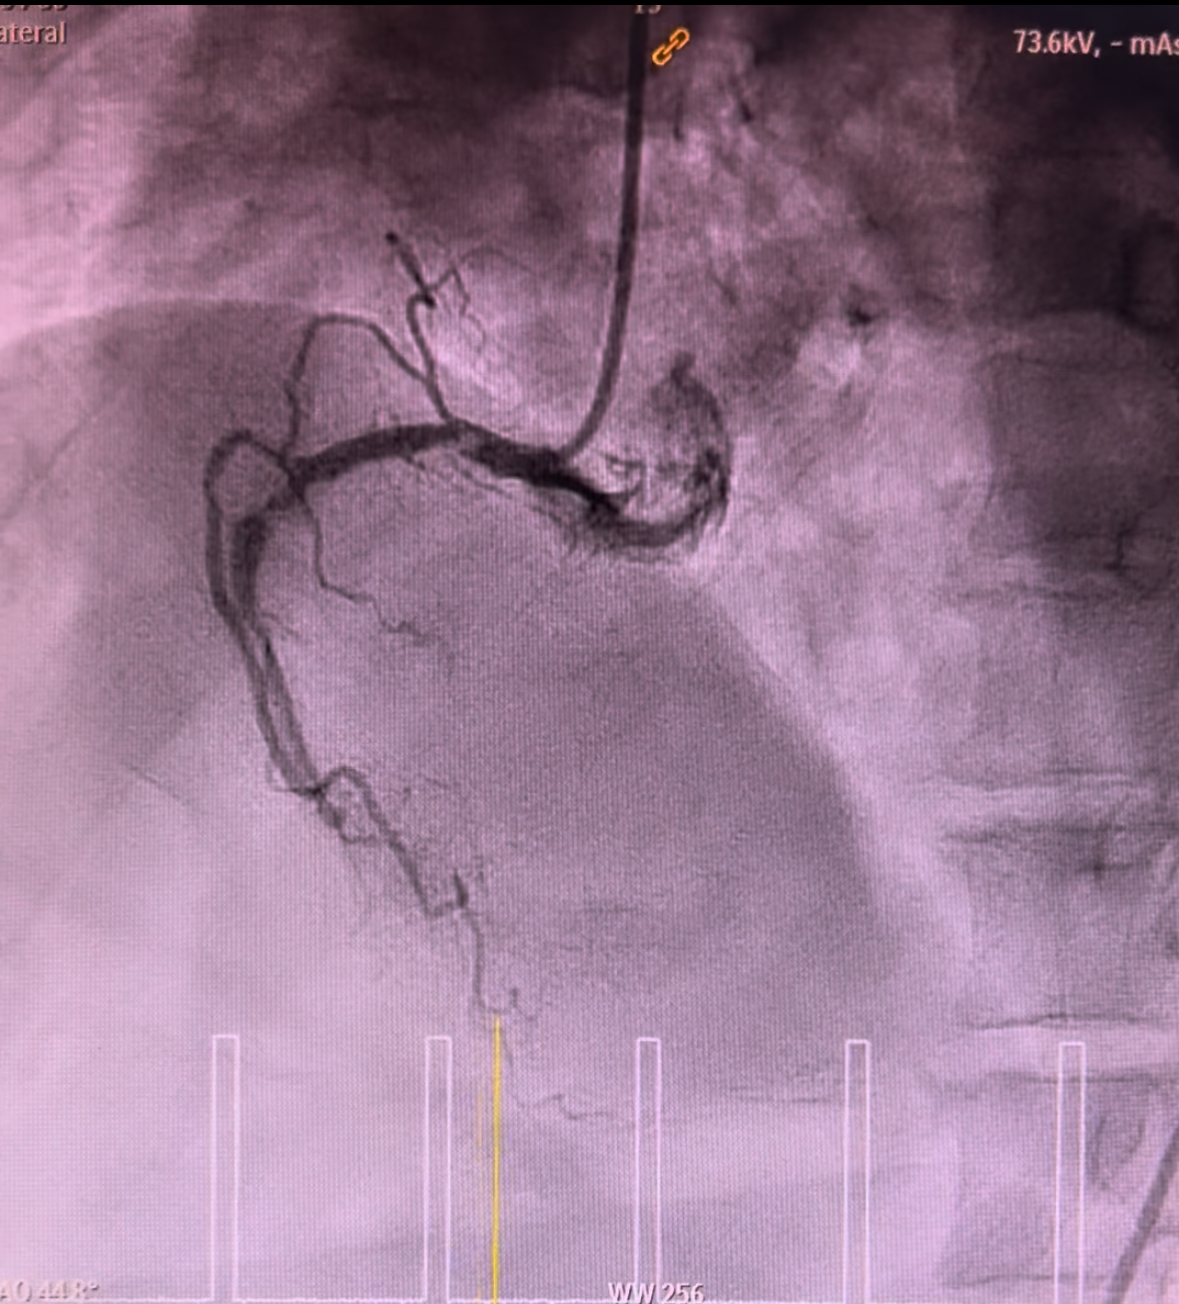

Coronary angiogram demonstrated smooth left main, 90% stenosis in the proximal left circumflex, 99% focal stenosis with severe calcification at mid LAD, followed by mild diffuse plaque until the distal end, and 90% stenosis at ostial D1. Right coronary was calcified with 80% stenosis at the proximal segment, 90% stenosis at the mid segment, and CTO at the distal segment. Discussion was held with cardiothoracic surgeons in which CABG was viewed incompatible.